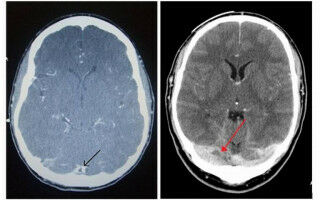

A new UCL and UCLH-led study of patients with cerebral venous thrombosis (CVT) following Covid-19 vaccination, provides a clearer guide for clinicians trying to diagnose and treat patients. The research, published in The Lancet, is the most detailed account of the characteristics of CVT, when it is caused by the novel condition vaccine-induced immune thrombotic thrombocytopenia (VITT).